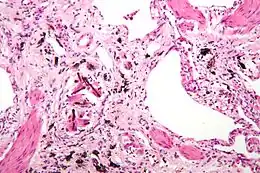

Description de cette image, également commentée ci-après

Photomicrographie d'asbestose (avec des inclusions caractéristiques), un type de pneumoconiose. Coloration à l'hématoxyline et à l'éosine.